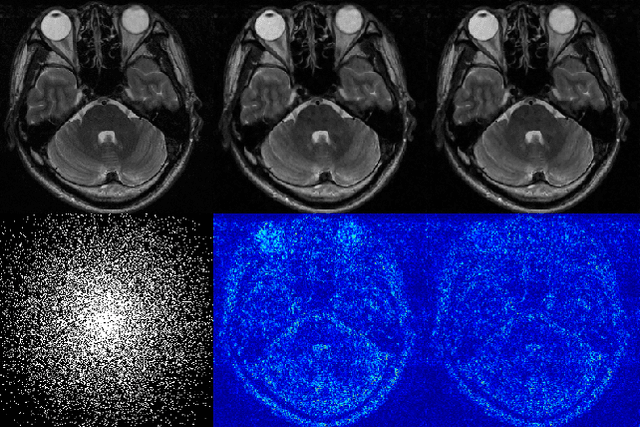

This paper proposes a multi-channel image reconstruction method, named DeepcomplexMRI, to accelerate parallel MR imaging with residual complex convolutional neural network. Different from most existing works which rely on the utilization of the coil sensitivities or prior information of predefined transforms, DeepcomplexMRI takes advantage of the availability of a large number of existing multi-channel groudtruth images and uses them as labeled data to train the deep residual convolutional neural network offline. In particular, a complex convolutional network is proposed to take into account the correlation between the real and imaginary parts of MR images. In addition, the k space data consistency is further enforced repeatedly in between layers of the network. The evaluations on in vivo datasets show that the proposed method has the capability to recover the desired multi-channel images. Its comparison with state-of-the-art method also demonstrates that the proposed method can reconstruct the desired MR images more accurately.